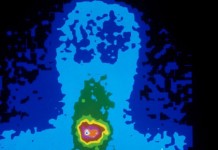

Злокачественные опухоли головы и шеи

Описание Средний возраст людей, у которых развиваются злокачественные опухоли головы и шеи (исключая злокачественные опухоли головного мозга, глаз и позвоночника), – 59 лет. Обычно злокачественные опухоли...

Злокачественные опухоли гортани

Описание Злокачественная опухоль гортани – наиболее распространенная болезнь после злокачественной опухоли кожи. Встречается в основном у мужчин и связана с курением и злоупотреблением алкогольными напитками. Эта злокачественная...

Рак щитовидной железы

Описание Рак щитовидной железы бывает четырех основных типов: папиллярный, фолликулярный, анапластический и медуллярный. Рак щитовидной железы чаще всего развивается у людей, подвергавшихся радиоактивному облучению области головы,...